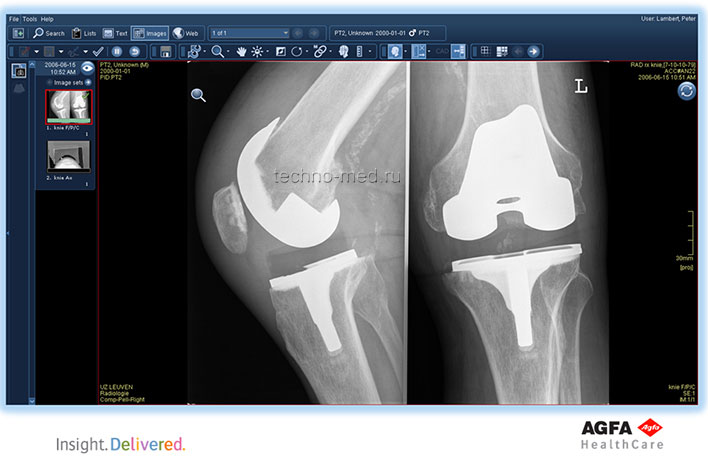

- Поддерживает непрерывный поток операций с изображениями во всех подразделениях предприятия;

Полный цифровой рабочий процесс для отделения визуализационной диагностики

| Дежурный приёмного отделения | Технолог | Рентгенолог | Фонотипист | Клинический врач |